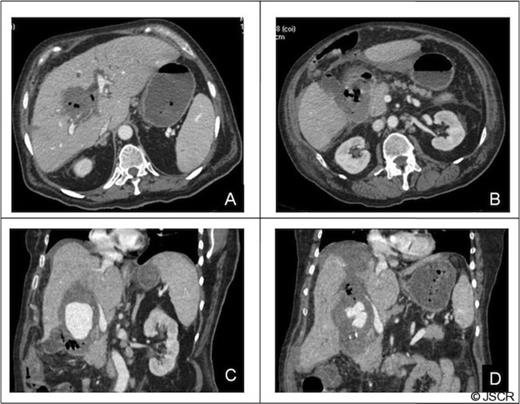

Forty-eight hours after admission the patient had an episode of haemodynamic instability suggestive of septic shock, which was also associated with a drop of 15 points in haematocrit levels (haematocrit: 24, WBC: 33 000). Empirical antibiotic therapy was begun and abdominal contrast-enhanced computed tomography (CT) was performed. CT showed a pseudoaneurysm of the right hepatic artery (RHA) of 7 cm in diameter, haemoperitoneum, intrahepatic dilatation of the biliary tree bile duct and the presence of hepatic infarction, and duodenal wall involvement (Figures 1 and 2).

CT of the abdomen: Complications of the pseudoaneurysm A, B) Hepatic infarction C)Duodenal wall involvement, D) Hemoperitoneum under right hemidiaphragm.